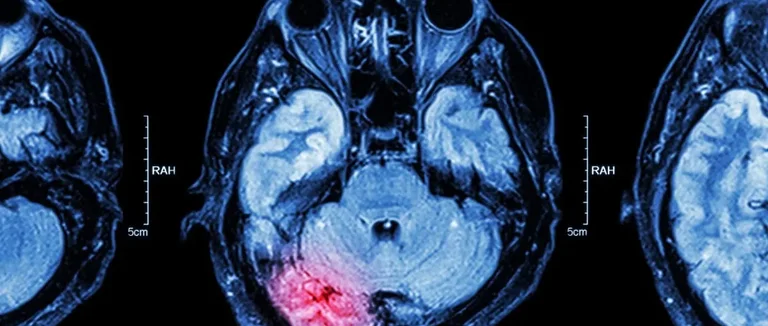

Методы визуализации (МРТ, КТ)

Современные методы визуализации, такие как Магнитно-резонансная томография (МРТ) и Компьютерная томография (КТ), важны для диагностики. МРТ показывает детали мягких тканей мозга, помогая выявить опухоли. КТ лучше всего показывает кровоизлияния, кальцификации и изменения в костях.